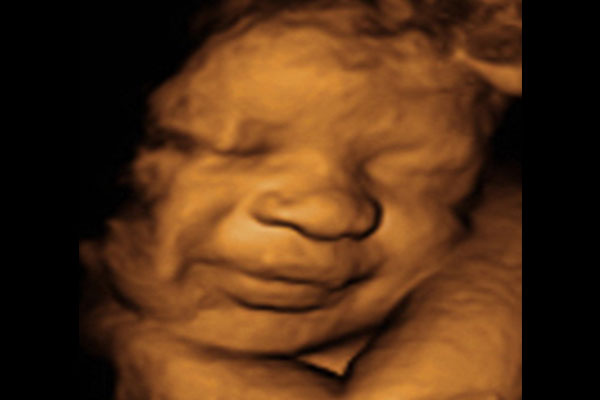

3D/4D Ultrasound

HD Ultrasound

8K Ultrasound